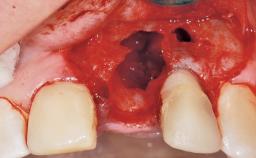

Immediate Flapless Placement of an Implant in a Maxillary Right Lateral Incisor Site

This 43-year-old male patient, a non-smoker, came to our practice because of a fracture of tooth 12 caused by a bicycle accident. Due to the combined para- and infrabony crown and root fracture, tooth extraction, and subsequent implant placement were suggested to the patient as the therapy of choice. The patient had high esthetic expectations with regard to the treatment outcome and asked for an immediate fixed provisional restoration. His individual esthetic risk profile summed up to a medium esthetic risk.

Placement Protocol Immediate implant placement

Tooth Site Maxillary incisor or canine

Socket Morphology Single-root socket

Socket Integrity Sufficient, with intact bone walls